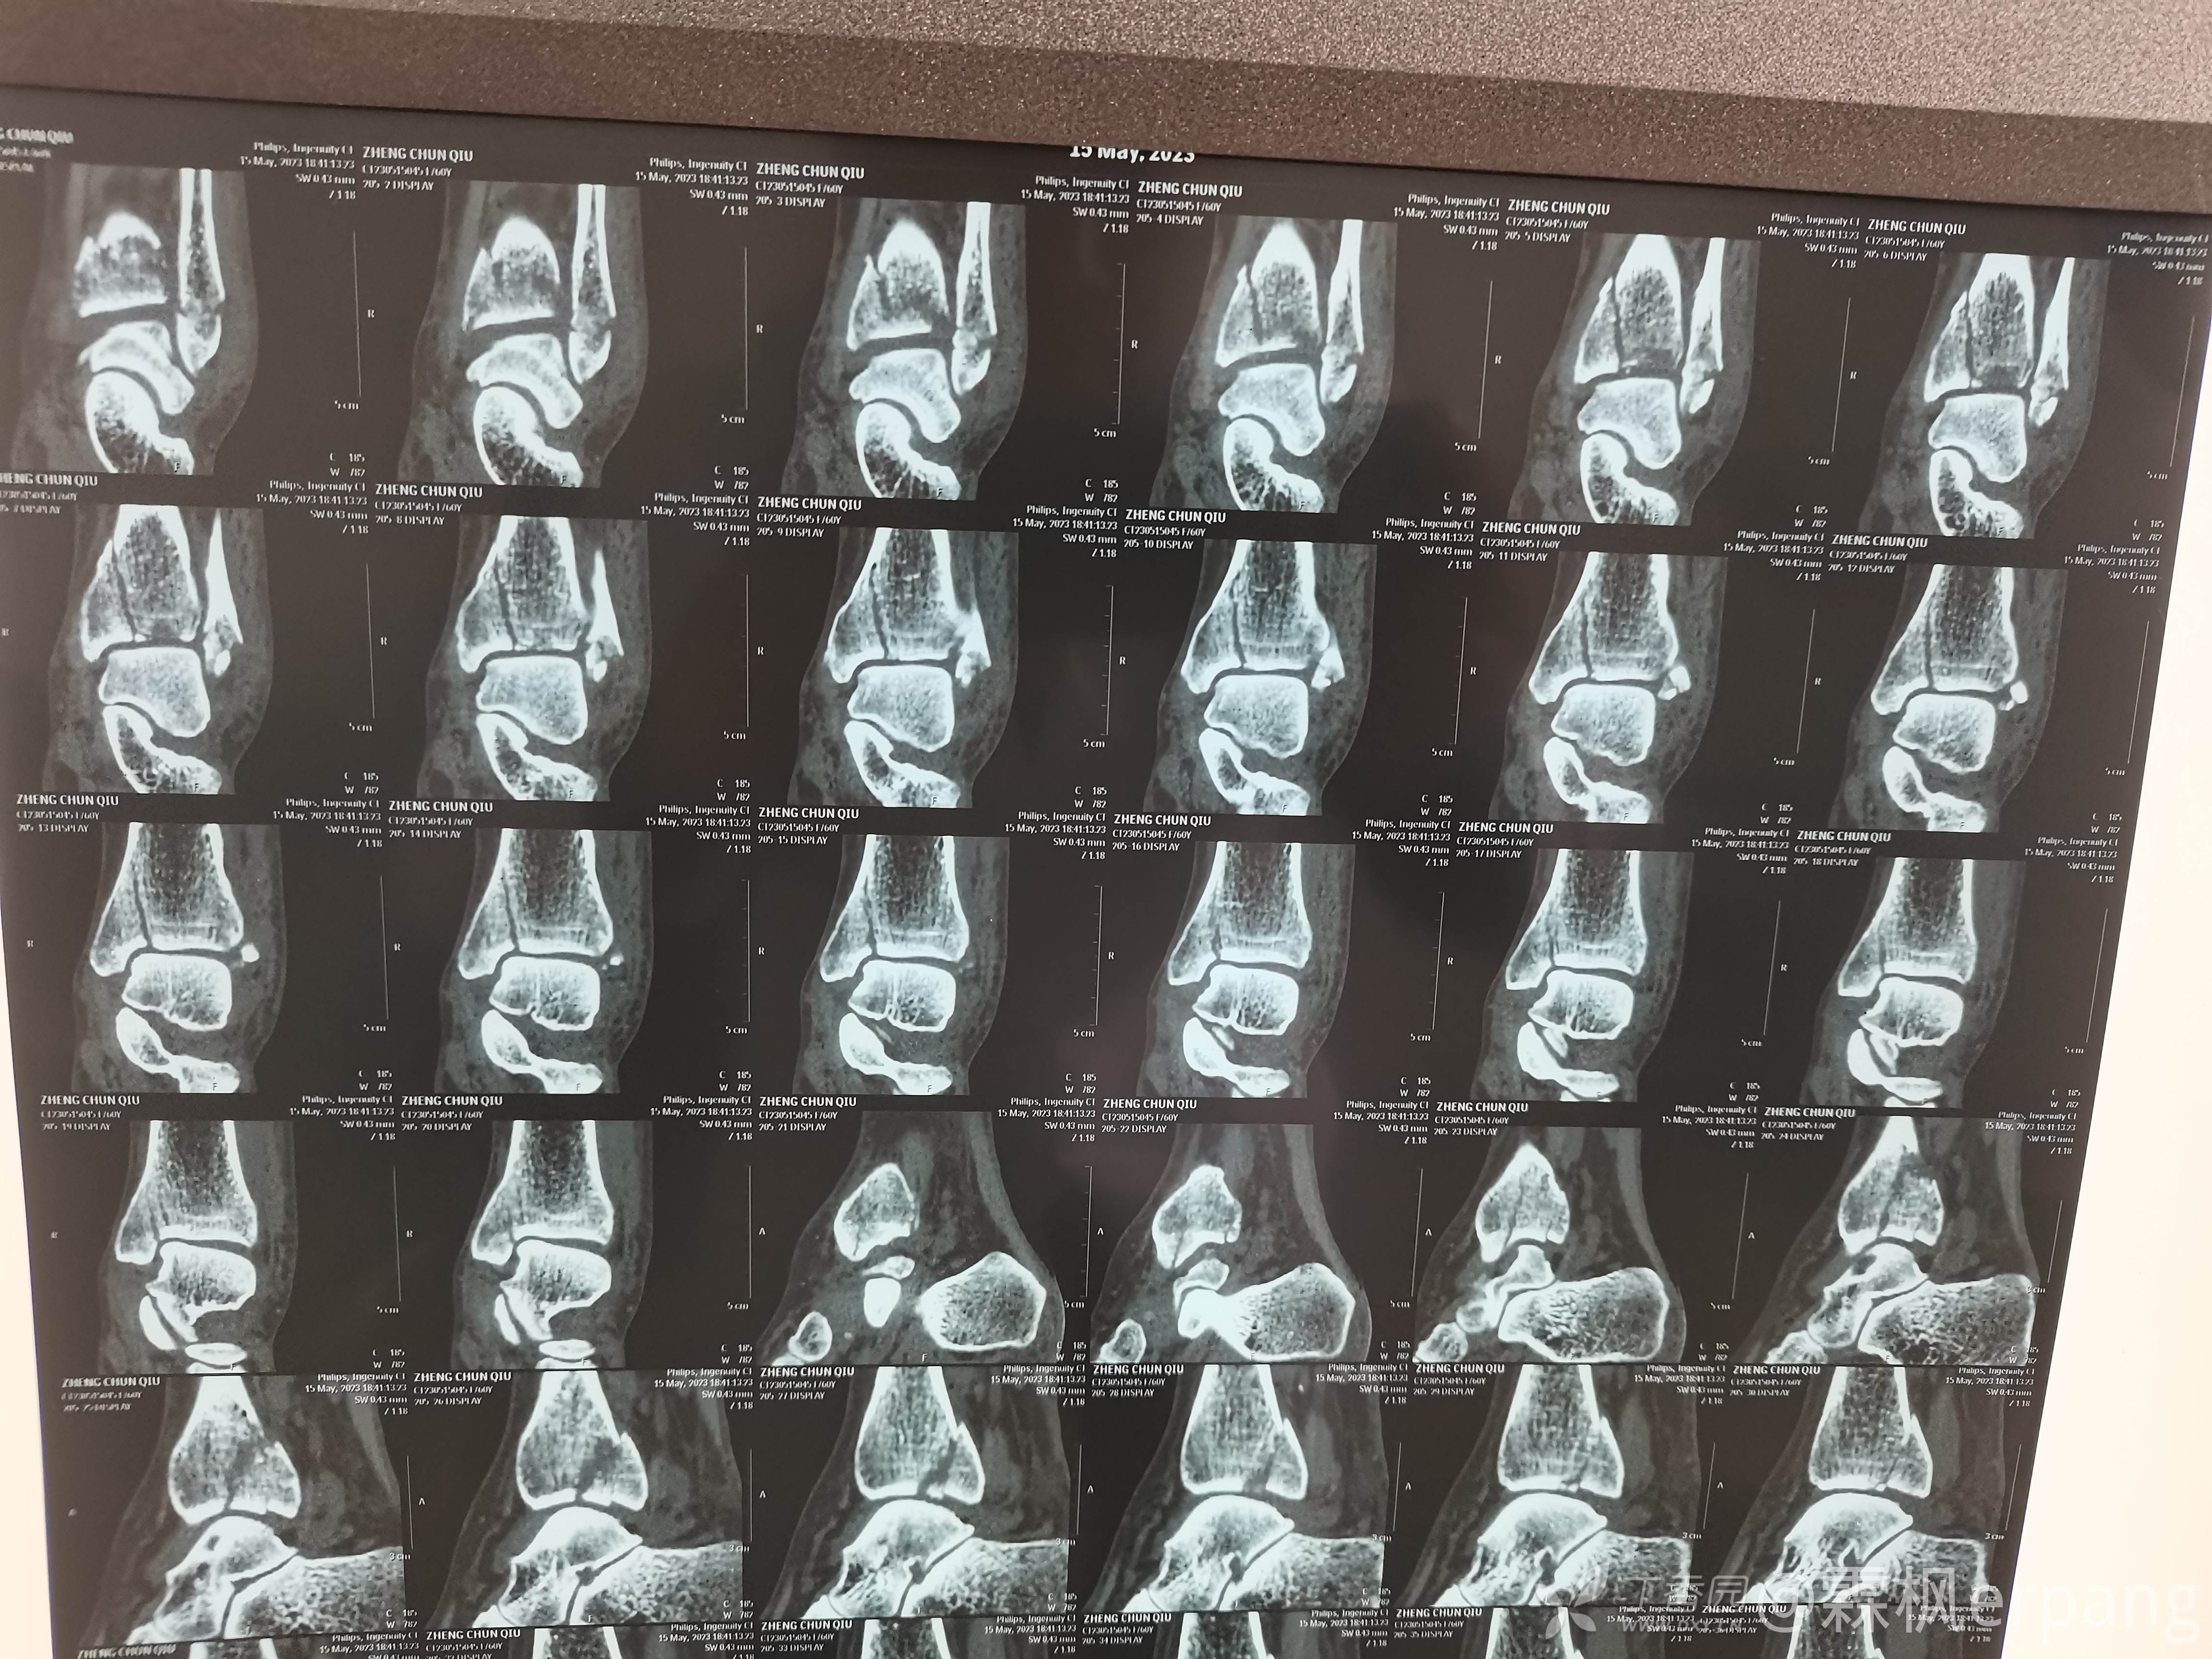

辅助检查:

正位以为没事呢

侧位变3度了

3度变4度